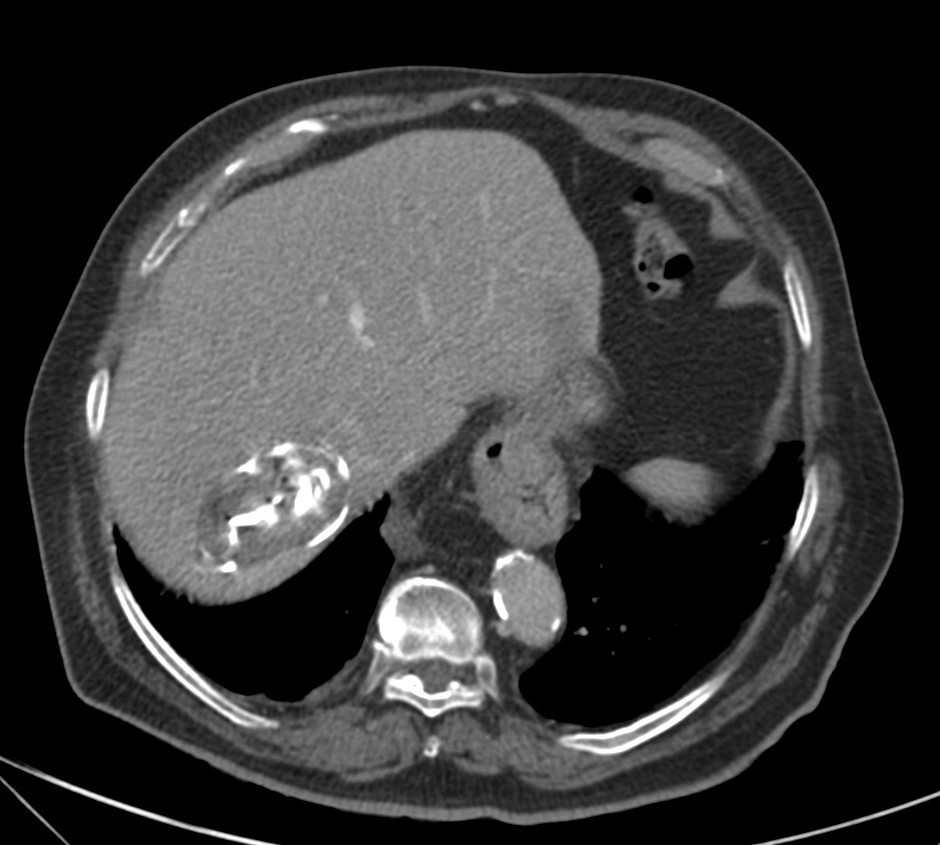

Paciente de 65 años al que se le realiza con dolor en hemitórax derecho más frebrícula:

Se procede a realizar un TC abdominal:

Elevación del hemidiafragma derecho una lesión quistíca de gran tamaño en segmento VII que continua con el segmento VI. Que pierde plano de clivaje con espacio pararrenal anterior

Estamos presenciando el lugar de afectación más frecuente de la Hidatidosis, el Hígado, concretamente sería el lóbulo hepático derecho, el cual se ha abierto al hemitórax derecho por una rotura directa.